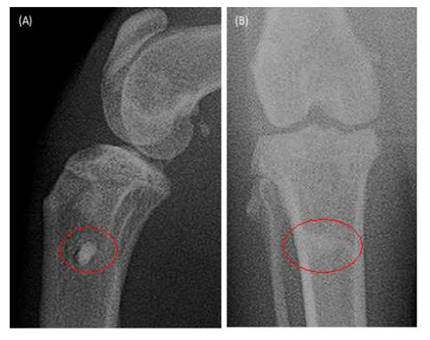

La radiografía posoperatoria del paciente felino a los 30 días de la cirugía (Figura 9), muestra una reducción notoria de la zona radiolúcida anteriormente comentada, lo que confirma que ya se presentan principios de osteointegración del implante en el hueso del animal y al no visualizar un perfil nítido en la imagen radiopaca del tornillo, se comprueba que la regeneración es inminente. Estas imágenes confirman que el procedimiento descrito en esta investigación es exitoso para la implantación de tornillos ortopédicos HA en los pacientes.